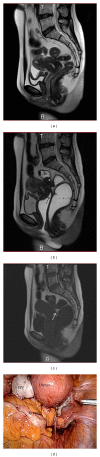

Objective: We conducted a single-center study to evaluate the usefulness of the magnetic resonance (MR) imaging jelly method for diagnosing endometriosis-associated adhesions in the Pouch of Douglas.

Methods: Thirty women with menstrual pain, dyspareunia, and chronic pelvic pain were enrolled in the study. All had been scheduled for laparoscopic surgery on the basis of pelvic and/or ultrasonographic (US) evaluation. All underwent MR imaging both with and without application of US jelly to the vagina and rectum. The images were compared and analyzed postsurgically in a random and blinded fashion by a radiology specialist and a radiology fellow. The radiologists' interpretations of the images were compared to the surgical findings recorded on DVDs.

Results: Adhesions in the Pouch of Douglas were found in 21 patients. The sensitivity and specificity of MR imaging without jelly administration were 85.7% and 55.6%, respectively, for the specialist and 81.0% and 55.6%, respectively, for the fellow; with jelly administration, values were 95.2% and 88.9% for the specialist and 90.5% and 66.7% for the fellow. Opacity produced by the jelly increased the sensitivity and specificity for both radiologists.